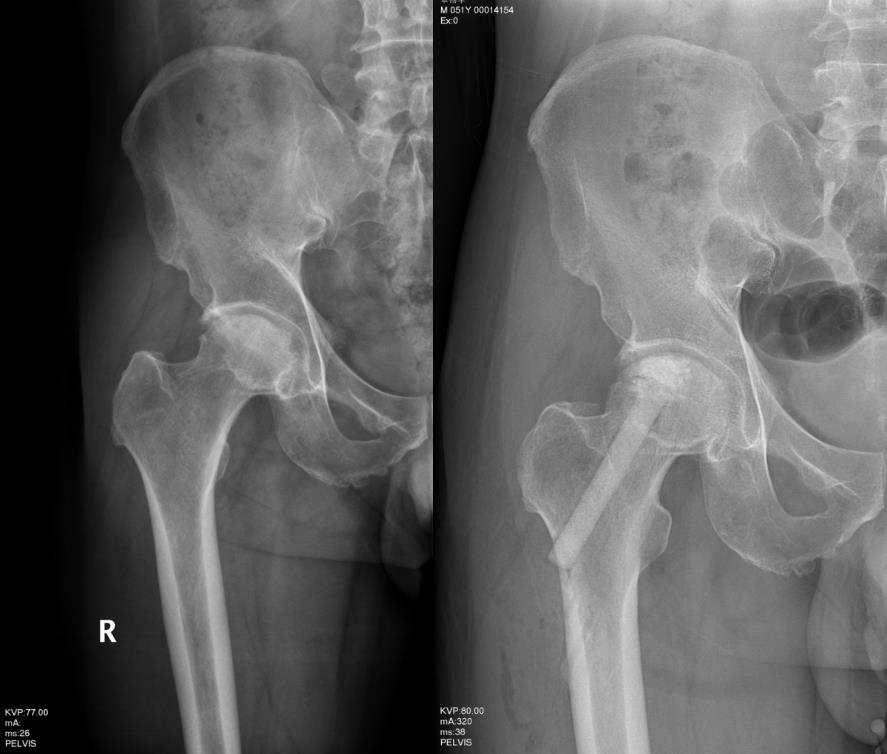

双侧股骨头坏死患者在我科行植骨保头手术治疗,一年后完全康复,现术后13年,双髋功能正常。图示为术前及术后3年的X光片。